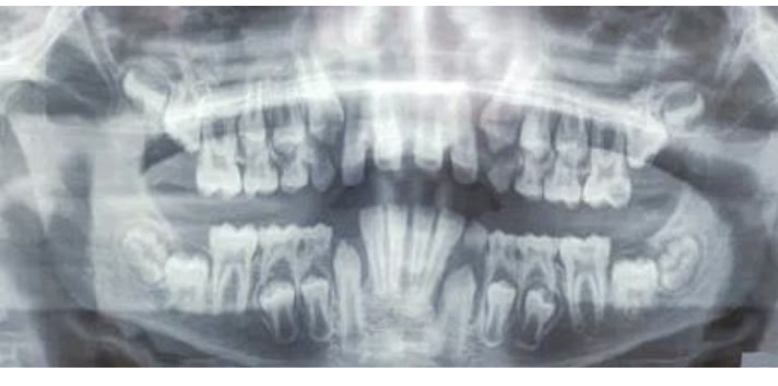

1.Lower adult CI there? YES. so def 6-7

1. Upper adult CI there (they normally erupt 7-8)? NO, baby ones should shed at 6-7.

Conc: pt. Is 6 y.o